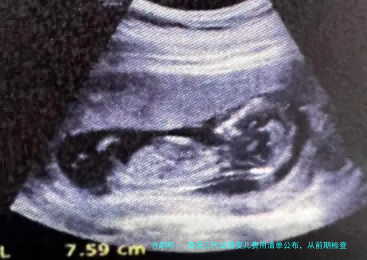

在正规进入试管婴儿周期此前,夫妻两方都需要进行一连串详细的身体检查,以评介生育本领和潜在风险。这些检查是订定个性化医治策略的基础,也是确保治疗安全和成功率的重点。

女性检查项目通常囊括:性激素六个项目(评估卵巢功能)、AMH(抗缪勒管激素,卵巢储备)、阴道B超(检查子宫、卵巢模样)、甲状腺功能、感染病筛查、染色体核型分析等。这一些检查的总花销大约在5000-8000人民币。